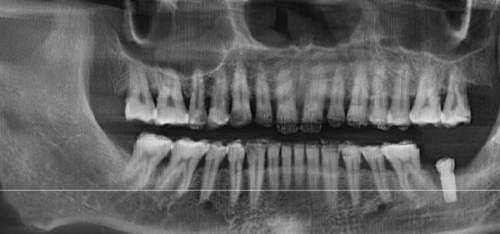

在进行单颗缺失种植修复前,他会对患者的口腔进行全方面的检查,包括牙齿的位置、牙槽骨的情况等。通过详细的检查结果,他能够正确判断患者是否适合种植牙修复。如果患者的牙槽骨条件良好,他会根据患者的牙齿形态、颜色等因素,选择合适的种植体和牙冠。

他擅长的项目众多,涵盖了单颗、多颗缺失种植修复、IV即刻负重、即拔即种等。对于各类GBR骨增量手术,他也有着丰富的经验。在面对复杂的口腔情况时,比如骨量不足的患者,他能够熟练运用骨增量技术,为种植牙创造良好的条件。此外,他还擅长常见牙周诊疗、牙列缺损的各类修复以及各种牙体牙髓的治疗等。